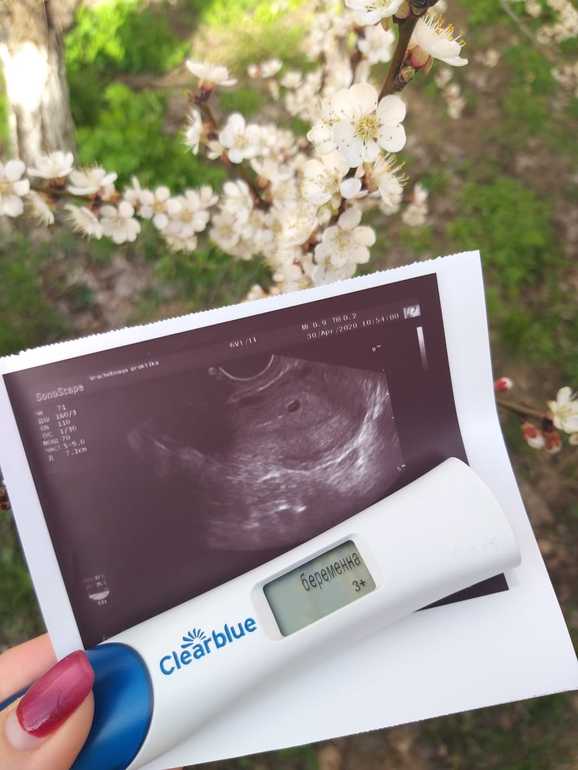

Ну вот и я добралась до 1 скринга. С малышочком слава Богу все хорошо по узи, развиваемся как надо, ручки, ножки..все на месте. Сердечко тарахтит как моторчик. Надеюсь и с генетикой все будет хорошо.

Просто хочу оставить эту красоту здесь на память. Наше маленькое-большое чудо.